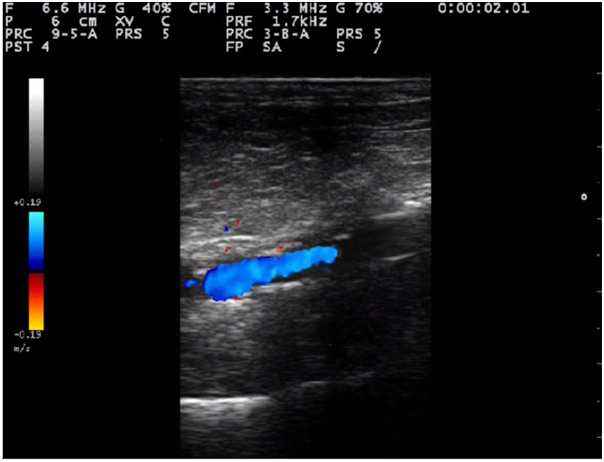

A 75-year-old Caucasian male with CLI on his right leg was admitted at our Institute fifteen months ago. He had a clinical history of COPD at GOLD C class, renal failure (preoperative serum creatinine 4.22mg/dL) and type 2 diabetes mellitus treated with insulin. Seven and six years before he had undergone endarterectomy and stenting of his right and left internal carotid artery, respectively. He was also affected by coronary artery disease which was previously treated with a coronary artery bypass graft and afterwards with implantation of drug eluting stent on circumflex artery for recurrent angina. The patient had been complained for right leg rest pain for 1month without ischemic ulcers or gangrene. Ultrasonography on his right leg showed the presence of a 10-cm occlusion at the mid third of superficial femoral artery (SFA) (Figure 1), with a poor distal flow which was recorded from the popliteal to the pedal artery. Both posterior tibial and peroneal arteries were occluded. On the left leg, both femoral and popliteal pulses were palpable. Transcutaneous oximetry on the first toe was 35mmHg on the right side and 58mmHg on the left side in a sitting position. The precise location of the occlusion after ultrasound mapping was marked preoperatively with a sign on the skin to facilitate the treatment in the operating room.

Figure 1 Preoperative color image of the lesion.